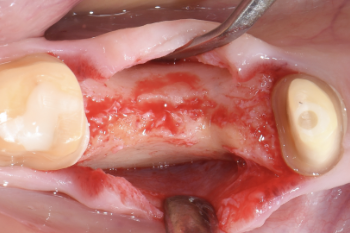

Fig. 6:

A full-flap was elevated to gain access to the bone.